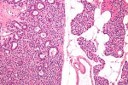

Figure 6.MEN1 syndrome designating a pancreatic polypetide secreting tumour with benign appearing adenomatous glands14.

MEN1 syndrome designating a                    pancreatic polypetide secreting tumour with   benign appearing adenomatous glands14.

Figure 7.MEN1 syndrome denominating a pancreatic neuroendocrine neoplasm with accumulation of benign, adenomatous glands15.

MEN1 syndrome denominating a               pancreatic neuroendocrine neoplasm with                accumulation of  benign, adenomatous glands15.